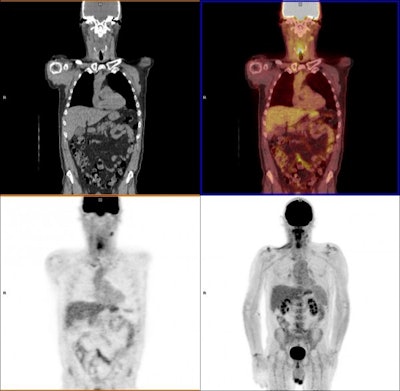

PET/CT scans show the remaining surviving cancer cells after treatment. Images courtesy of University of Birmingham.Patients who had significant FDG uptake on PET/CT scans after 12 weeks of treatment were classified as having an incomplete nodal response, while mild or no FDG uptake in enlarged nodes or mild FDG uptake in normally sized nodes was considered an equivocal response. These patients subsequently underwent neck dissection. All other results were deemed complete responses to therapy.